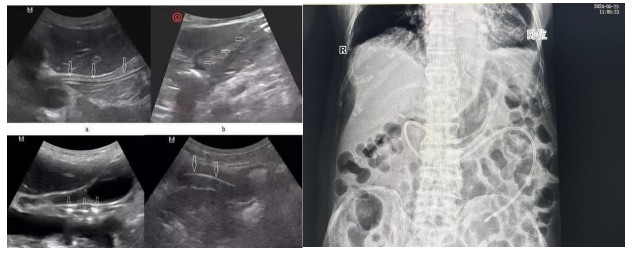

經(jīng)腹部X片驗(yàn)證一個(gè)完美的大“C”呈現(xiàn)出來,確認(rèn)鼻空腸管已經(jīng)達(dá)到指定位置。

B超引導(dǎo)下營養(yǎng)管置入術(shù)相比內(nèi)鏡輔助下營養(yǎng)管置入,通過二維顯像觀察鼻腸管的位置,無創(chuàng)監(jiān)測,定位準(zhǔn)確,提高了置管的成功率,能有效減少置管給病人帶來的不適體驗(yàn)及不必要的損傷。營養(yǎng)支持已成為重癥患者綜合治療重要環(huán)節(jié),對重癥患者預(yù)后起著關(guān)鍵作用,新喂養(yǎng)途徑的建立,讓腸內(nèi)營養(yǎng)支持順利的開展,不僅減少了患者的痛苦,也為重癥營養(yǎng)支持治療開辟了一條嶄新的補(bǔ)給通道。